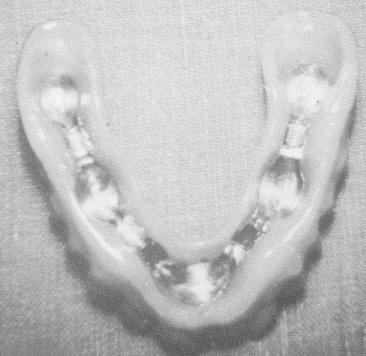

Fig. 10-228. A mesostructure framework consisting of five gold copings joined together with a connecting bar.

Fig. 10-229. The completed palateless denture with internal clip bars which secured it to the connection bar of the mesostructure. (From Linkow, L. I.: Maxillary endosseous implants, Dent. Concepts 10 [1] :14-24, 1966.)